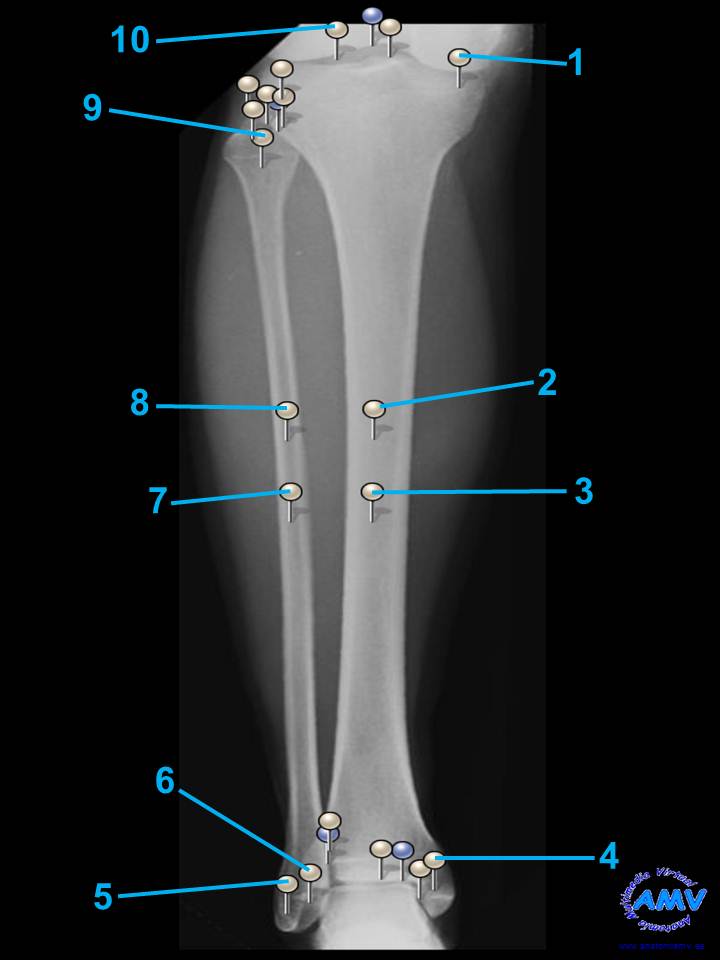

Radiografía de la Pierna

rx_mi_07.jpgIndique que estructura se señala con el número correspondiente:

El nº 1 señala .

El nº 2 señala .

El nº 3 señala .

El nº 4 señala .

El nº 5 señala .

El nº 6 señala .

El nº 7 señala .

El nº 8 señala .

El nº 9 señala .

El nº 10 señala .